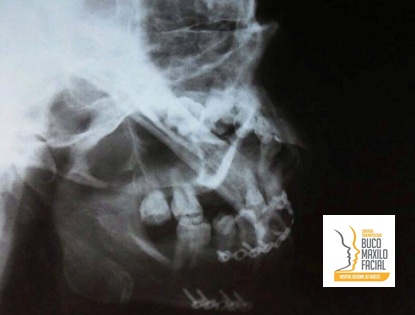

Momento em que o professor Belmiro Cavalcanti palestra sobre reconstruções da ATM

Prof Marconi Maciel em sua palestra sobre anatomia aplicada da ATM